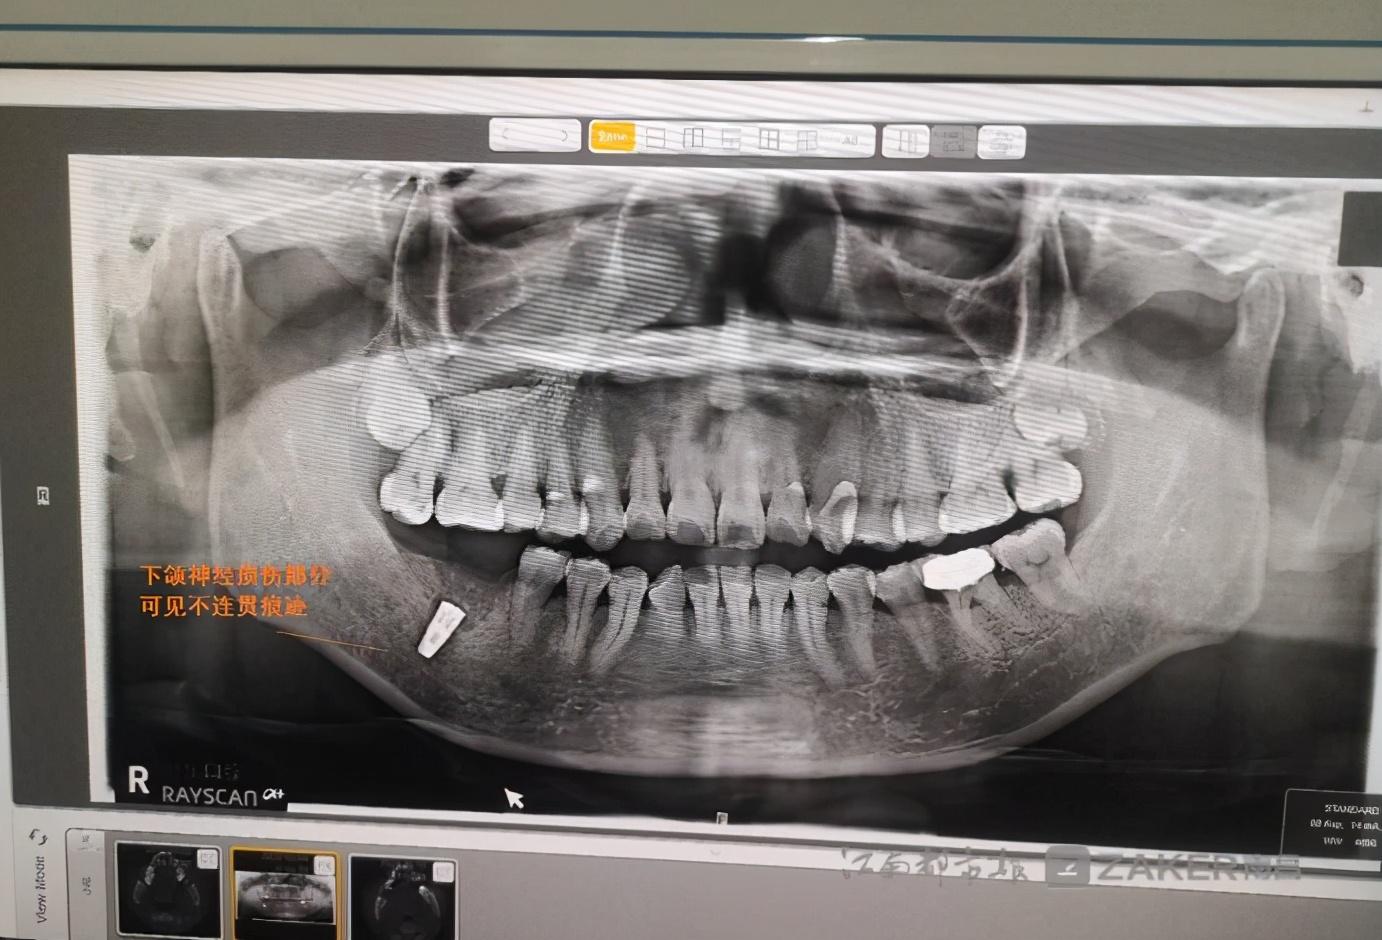

消炎針打完后,下頜的麻木感仍然存在。在家人的陪同下,繆女士前往專業(yè)口腔醫(yī)院檢查。在一份由南昌大學附屬口腔醫(yī)院 9 月 29 日出具的診斷證示,"46 牙可見種植體植入影像,下頜神經(jīng)管上壁可見不連續(xù)影像。" 繆女士告訴記者,經(jīng)檢查診斷后得知,自己的下頜神經(jīng)因種植牙手術受到損傷,這是下頜麻木的根本原因。